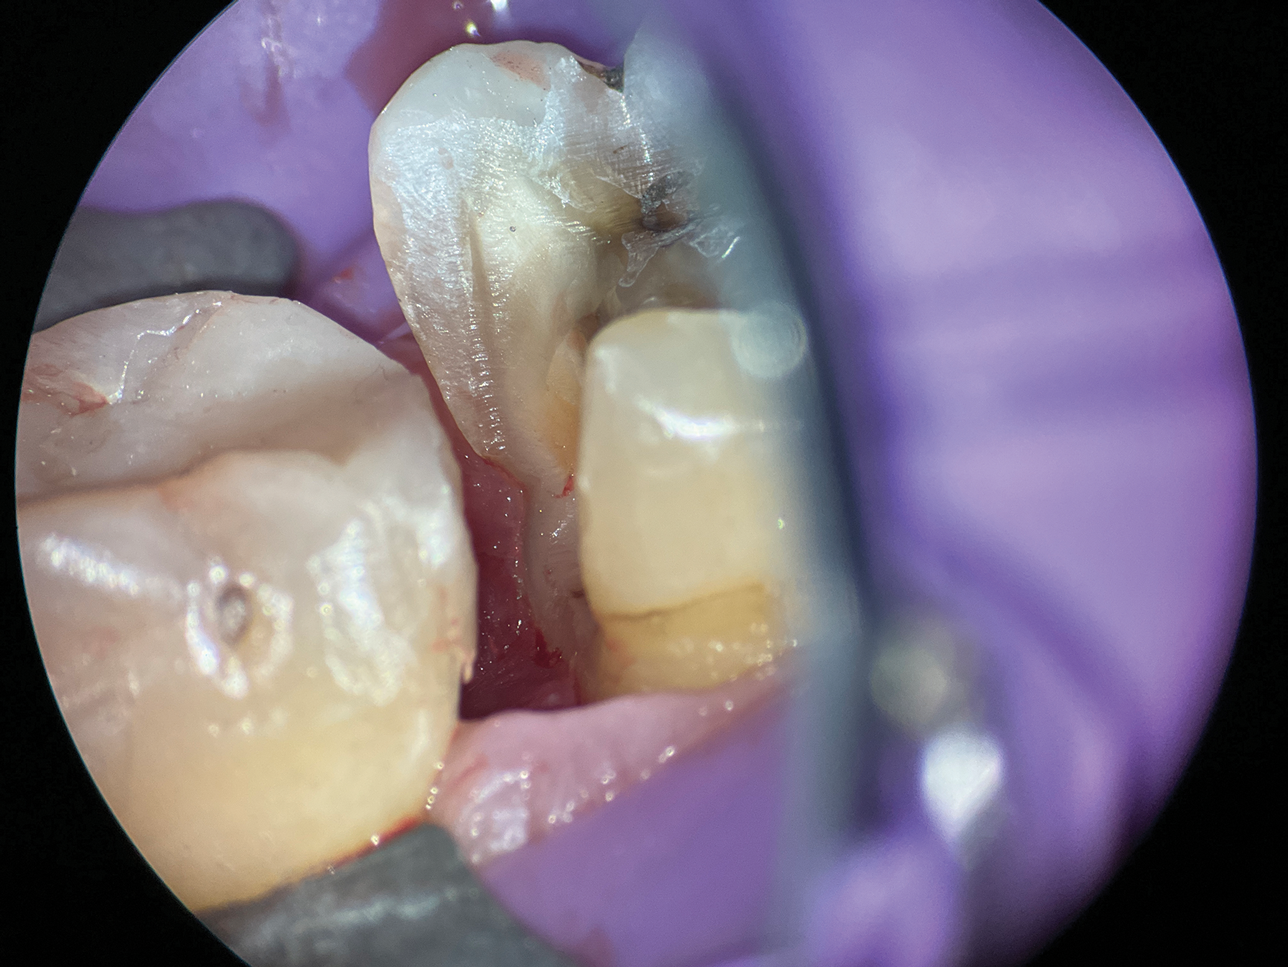

(13.) A wide 2-mil copper band was placed as an additional matrix to create absolute isolation, effectively sealing the space between the Tofflemire matrix and the margin.

Figure 13